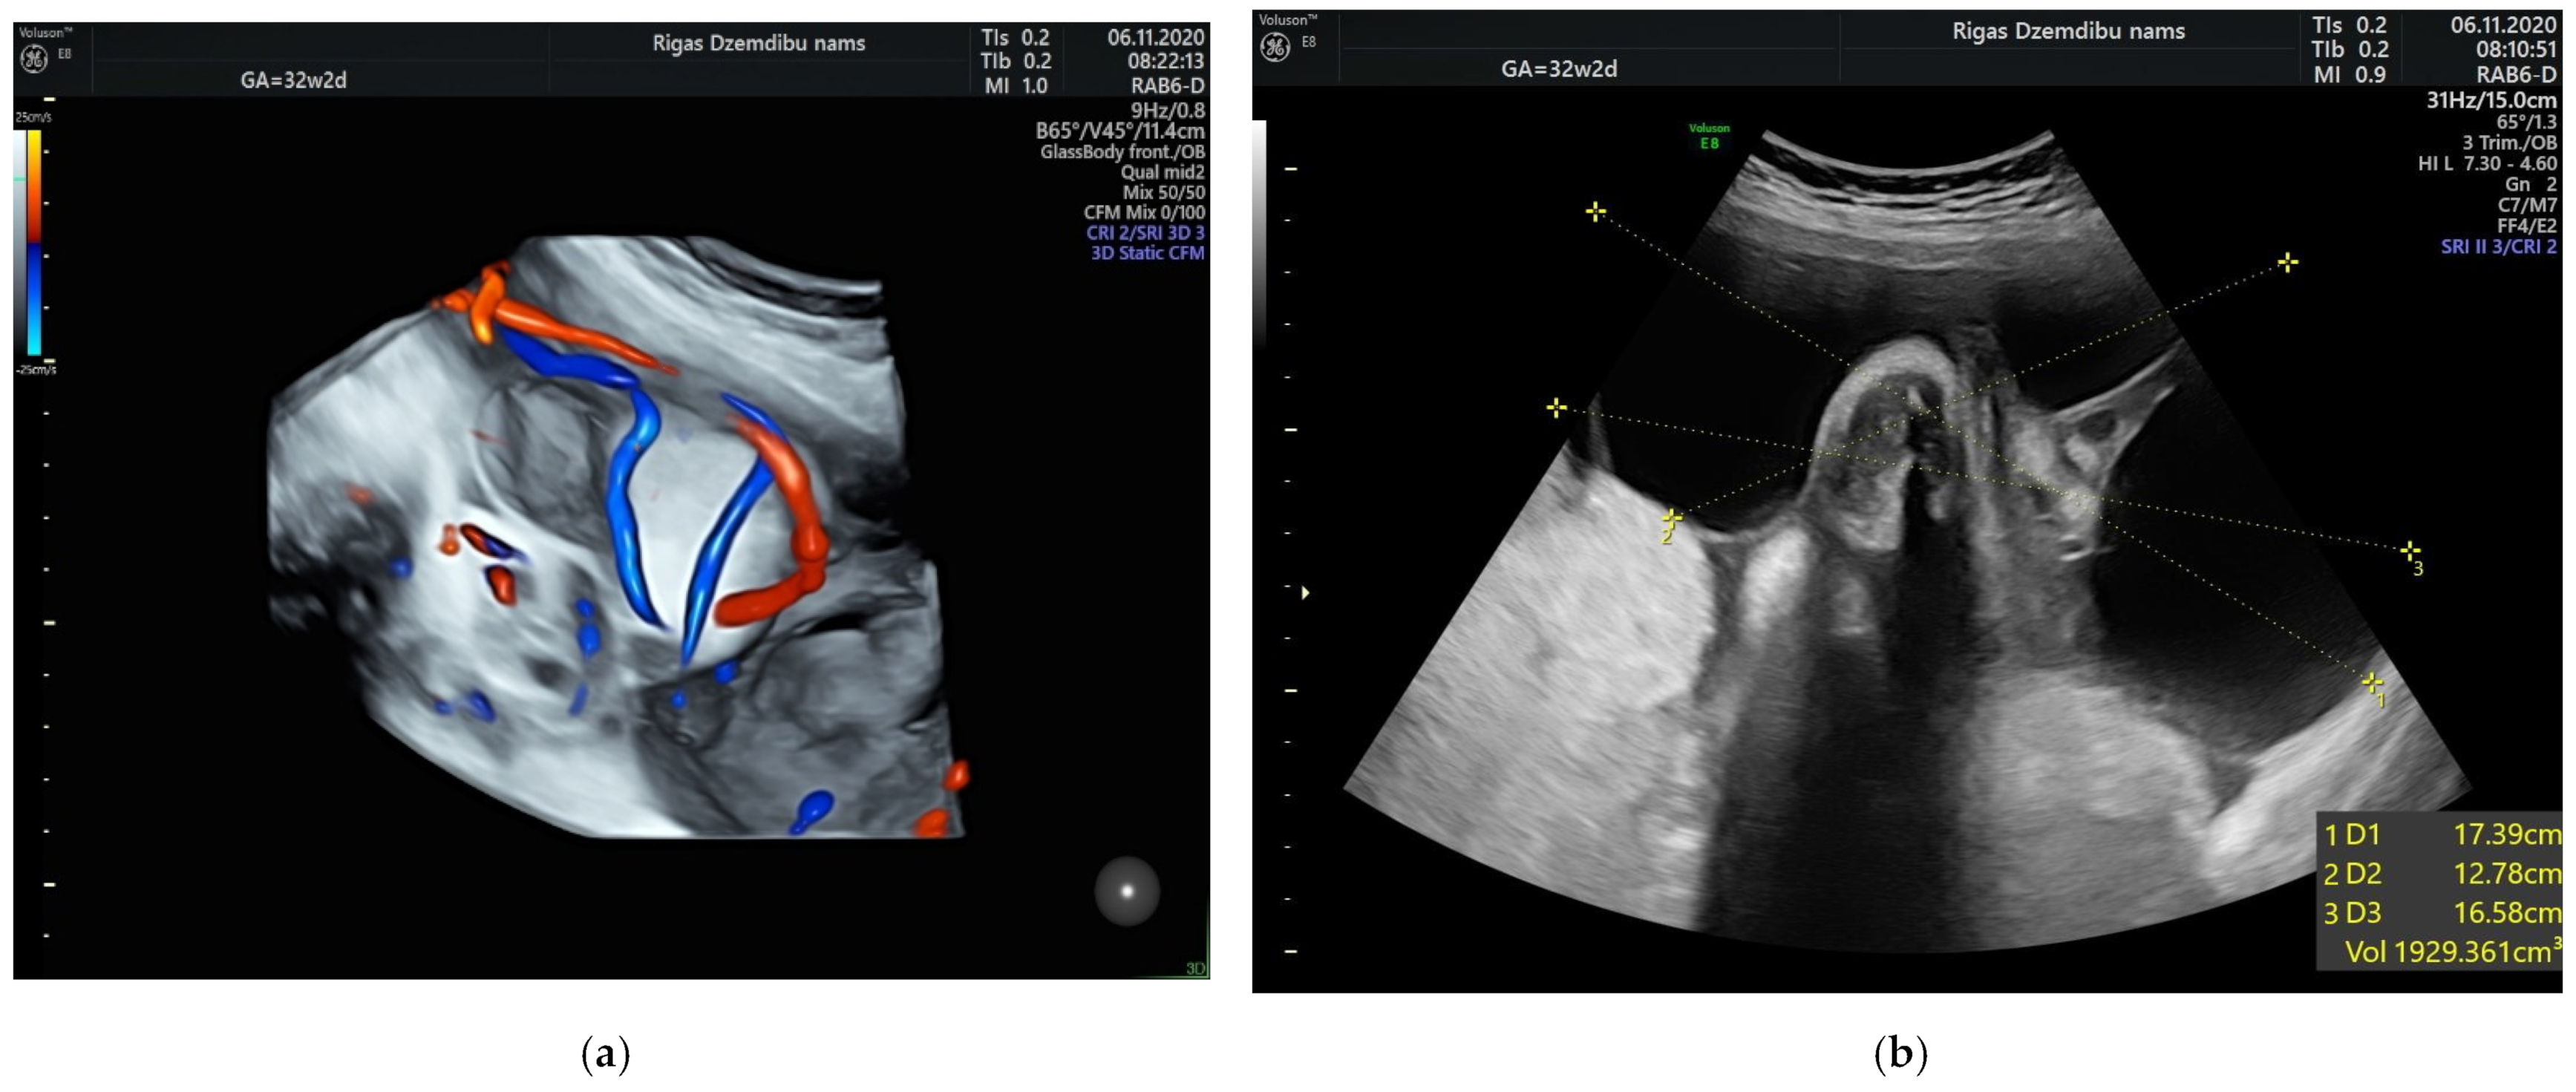

The size of the solid component was 3.4 × 2.3 cm and did not change during the pregnancy. The umbilical arteries and vein were running around and through, extra vessels were not observed in the tumor (Figure 2a). At the follow-up, the mass had rapidly enlarged in the size, from 285.32 cm3 at 26 weeks to 1929.36 cm3 at 32 weeks (Figure 2b). As well the reduction of fetal growth was observed from 30th week of gestation (Figure 3b).

Figure 2.

(a) Umbilical vessels going through the tumor at 32 + 2 weeks by 3D static HD flow (glass mode) imaging; (b) Tumor appearance at 32 + 2 weeks.